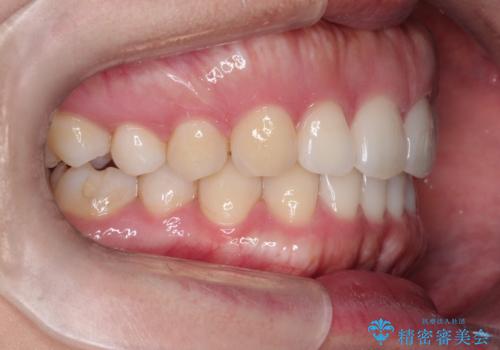

- 前歯の歯並びの改善を希望され来院された患者様です。

初診時の歯並びの状態としては、下顎前歯に及ぶの中等度のがたつき(叢生)があり、前歯が深く噛みこんでいる状態でした。

抜歯は行わず歯列弓の拡大やディスキング(歯と歯の間の隙間を作る処置)を行い叢生を改善しました。

見た目、嚙み合わせ及び、治療期間や施術内容に大変ご満足いただきました。